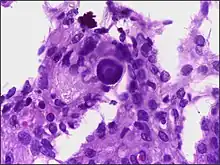

Dois corpos de psammoma (roxo escuro) em carcinoma seroso peritoneal